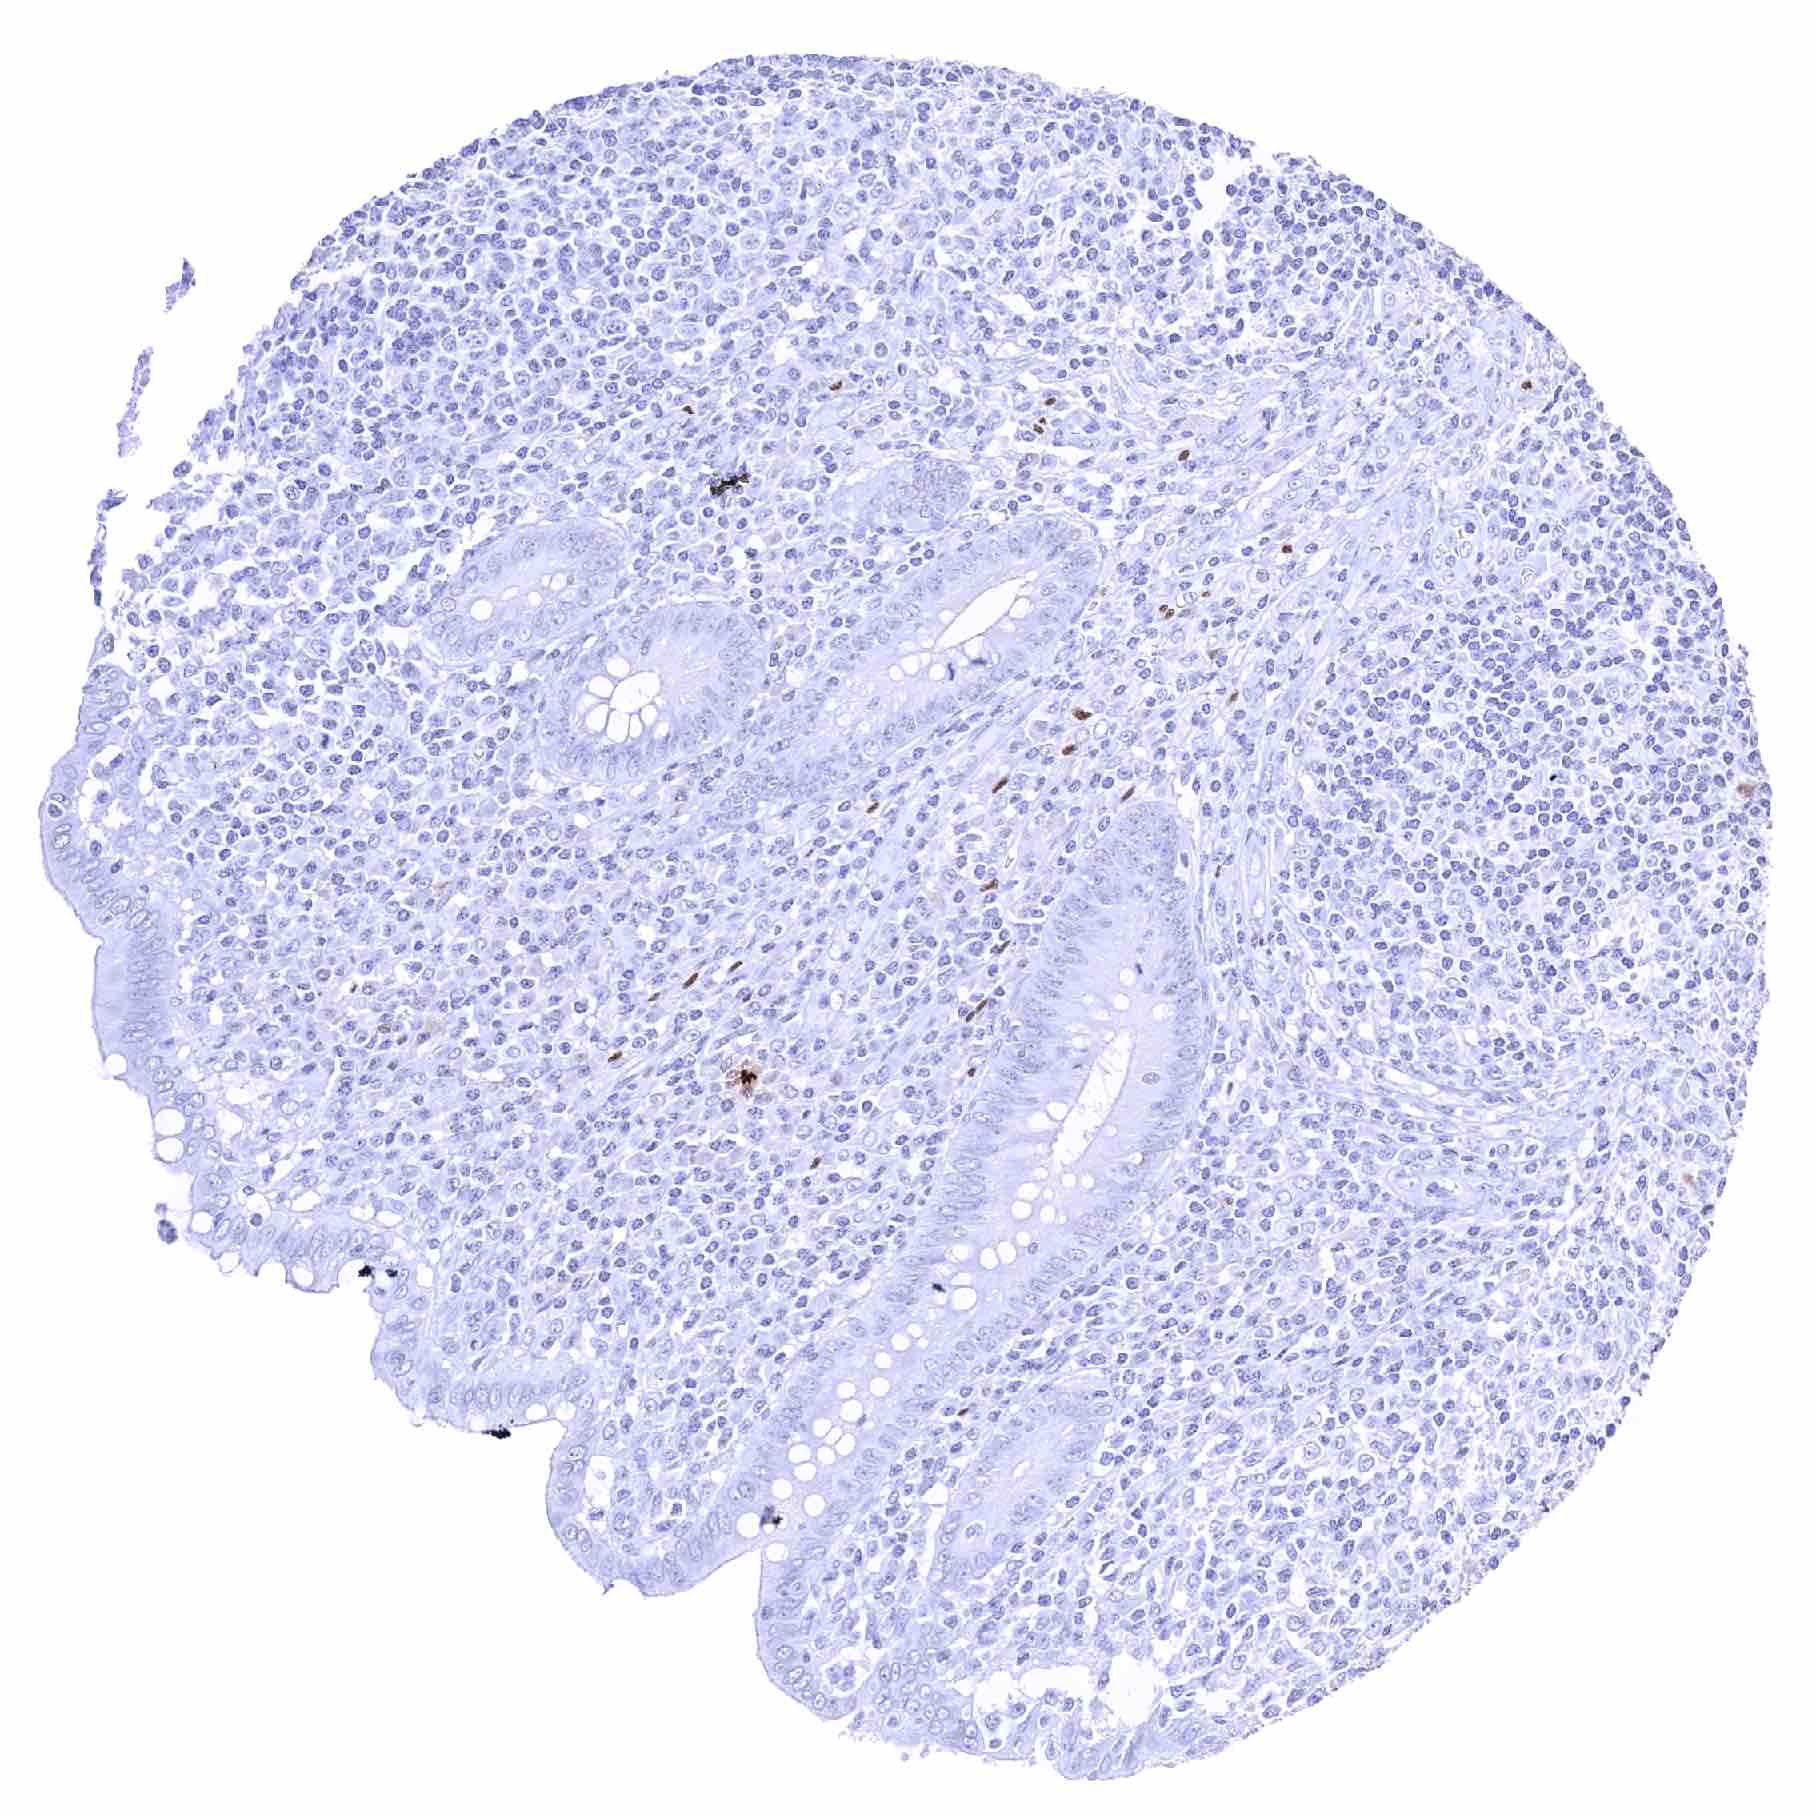

Tonsil – Weak to strong SOX2 positivity of a fraction of squamous epithelial cells in crypts

Tonsil, surface epithelium